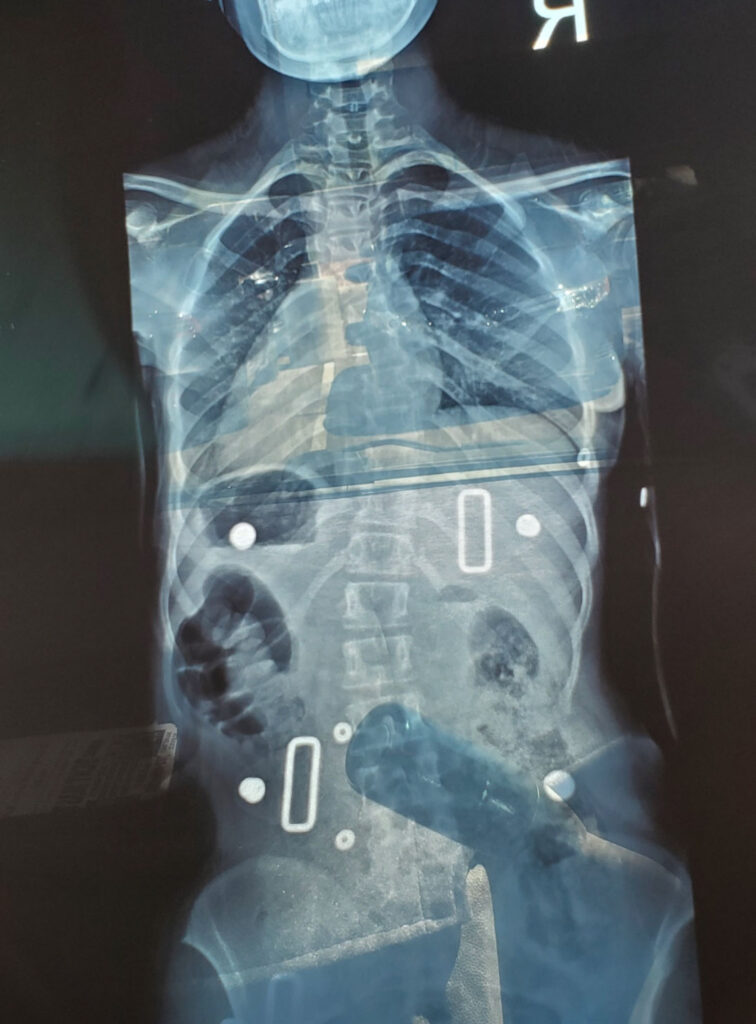

At my appointment, they gave me a gown to change into and took me to the x-ray room. The machine was very simple, like a camera, that had a light shining on me. Standing in front of the machine, I could feel my eyes starting to water because of how scared I was, but I held it together and continued on with the x-ray, as I refused to cry in front of the nurse. After my x-rays, my doctor measured my curves on my thoracic and lumbar. My thoracic was the worst of the two curvatures and was curved at 40° and was progressively getting worse. They suggested I get a brace until we decided what we wanted to move forward with. A month later, I was given a back brace, and my options were very limited. I had a choice to do nothing and risk my spine getting worse, wear my brace until I was 18 and then get the surgery, wear my brace until I stop growing, or get surgery as soon as possible.

The brace was so unbearable to wear, that I would cry every time I put it on. I was told the brace wouldn’t fix my problem, but it would hopefully stop my spine from getting worse. I didn’t want to wait until I was 18 because I didn’t want to risk my spine getting worse, and having my movement become limited in the future. So, my last two options were to get a Spinal Fusion or a Vertebrae Body Tethering (Tethering/VBT). A spinal fusion is a surgery where bolts and rods are placed in your spine to keep it aligned, while Tether is a “rope” that is attached to screws on the vertebrae which goes along the side of the spine to keep it aligned.

My biggest fear was getting a Spinal Fusion because I didn’t want my spine to be completely fused from my thoracic to my lumbar because my motion would be limited. Luckily, I was told they would only have to fuse my thoracic, and hopefully my lumbar will follow as I grow. I would still be limited, but the change wouldn’t be so drastic, and there was still a possibility that my lumbar could get worse. After a few more days to think about the decision, we scheduled the appointment and I was due for surgery on December 16, 2020.